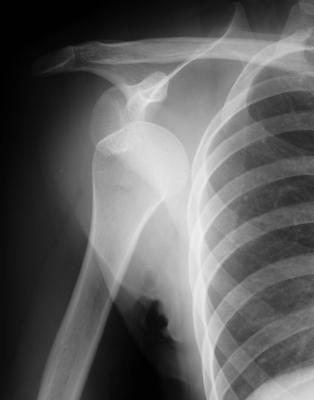

肩锁关节脱位:

1.病因:直接暴力:多见,侧位摔倒,例如骑摩托车摔倒,踢足球摔倒等;间接暴力:少见,牵拉或坠落伤。2.分型:I型:关节囊、韧带未断裂,II型:关节囊破裂、半脱位,III型:关节囊、韧带完全断裂。3.临床表现:症状:肩部疼痛,患侧上肢上举或外展时疼痛加重,体征:肩锁关节局部压痛或出现畸形。肩峰外侧端隆起,向下推压出现反弹性的琴键征(piano sign)–提示肩锁关节完全性脱位。4.治疗:Ⅰ型:支具或吊带固定2-3周,尽早行轻柔功能锻炼,防止关节僵硬。Ⅱ型:治疗原则同Ⅰ型,若症状不减则需行手术治疗。Ⅲ型:手术治疗。